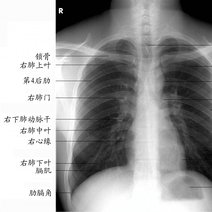

白肺的意思是指胸片、CT上发现正常肺组织透X线是黑色,只有心脏和大血管是白色,但是由于各种疾病、各种致病因素,导致两肺野呈大片的密度增高,出现白色的阴影,就...47600人收听

白肺一般是指重症肺炎在X光检查下的表现,肺部呈现一大片的白色状态而闻名。形成白肺一般都预示着肺部被炎症所广泛浸润,引起白肺的病因往往非常复杂,并且来势凶...28117人收听

白肺是指患者在X光胸片检查或者肺部CT检查中,肺部间质组织呈现大片状白色状病变的表现。白肺的症状表现多发生于重症肺炎,因为肺部间质组织持续性受到病毒、细...60057人收听

白肺(White lung)是一种临床综合症,其特征是重度肺炎患者的肺部积累了大量渗出物,影响多个肺叶,使肺部影像学检查呈现出大范围的白色区域。病因多为新型冠状病毒感染、细菌性肺炎、中东呼吸...

[最佳答案] 白肺是放射学名词,所谓白肺是指胸片或者CT上弥漫的高密度影,使得片子看不到肺纹理。导致白肺发生的原因很多,常见的大叶性肺炎、肺水肿,或者是病毒性肺炎比如SARS,以及流感、病毒引起的肺炎都会导致白肺。 至于能不能治愈要根据疾病的不同来决定, 白肺是放射学名词,所谓白肺是指胸片或者CT上弥漫的高密度影,使得片子看不到肺...